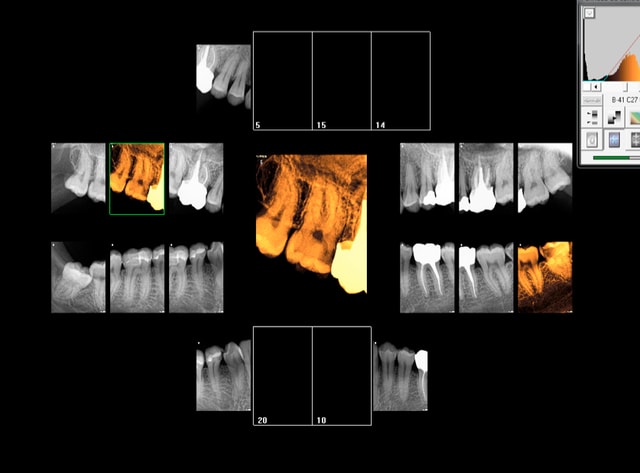

Rebelote aujourd'hui. Pulpite sur 15.

Re re belote. pulpite 38. -))))

Pas venu depuis 2007 date de la pose d'onlays sur 45 46.

On va pas refaire le débat, mais ou bien je suis un mutilator, ou bien je suis lobotomisé, mais il ne me semble pas aberrant de poser IC/Cr sur cette 15 non ?, je me vois pas y coller un onlay.

Après Chicot, on a les mêmes qui consultent quand ça picote sérieux, et en général l'indication du coiffage MTA,biodentine/inlay/onlay, n'est plus vraiment d'actualité.

En général c'est déjà limite pour la couronne alors ...

Suivant : 47 pétée en distal mais pas de douleur ( dernier RDV 2008) . Chiotte elle pouvait pas attendre un peu avant de péter ? j'aime bien les actes qui solvabilisent à la fois le patient et le praticien pas ces soins opposables à un tarif de merde. -)))

Ah ! enfin une endo au résultat non aléatoire sur 36 ! spéciale dédicace pour améli ! -))))

Suivant : 45 cassée ( jadis un onlay support de bridge ? ) Dent gardée vivante puis endo à travers l'onlay je suppose. ca marche moins bien après forcément. -))))

Maintenant la question que je me pose , vais je continuer à soigner les caries moyennes révélées ailleurs par les radios ? Vu qu'on nous prend pour des cons, hein ?

En plus faire les radios et les coter c'est prendre le risque de se faire emmerder par un CDC, autant ne plus en faire non ? ca résoud le problème de conscience que je pourrais me poser à l'avenir ! Il suffira d'attendre les signes d'appels et d'avoir des stocks de R25 ! -))))

Suivant : douleurs 36. Abcès du à un Syndrome du septum dent vivante, dommage.......-)))))

Dernier rendez vous chez le dentiste : 12 ans ( extractions des sagesses)

Notez l'indication des rétro coronaires et de la rétro alvéolaire dans ce cas : pas d'antécédents de soins intensifs et atteinte pulpaire suspectée ( élimination d'un 4ième degré, fais le test au froid après) . -)))))